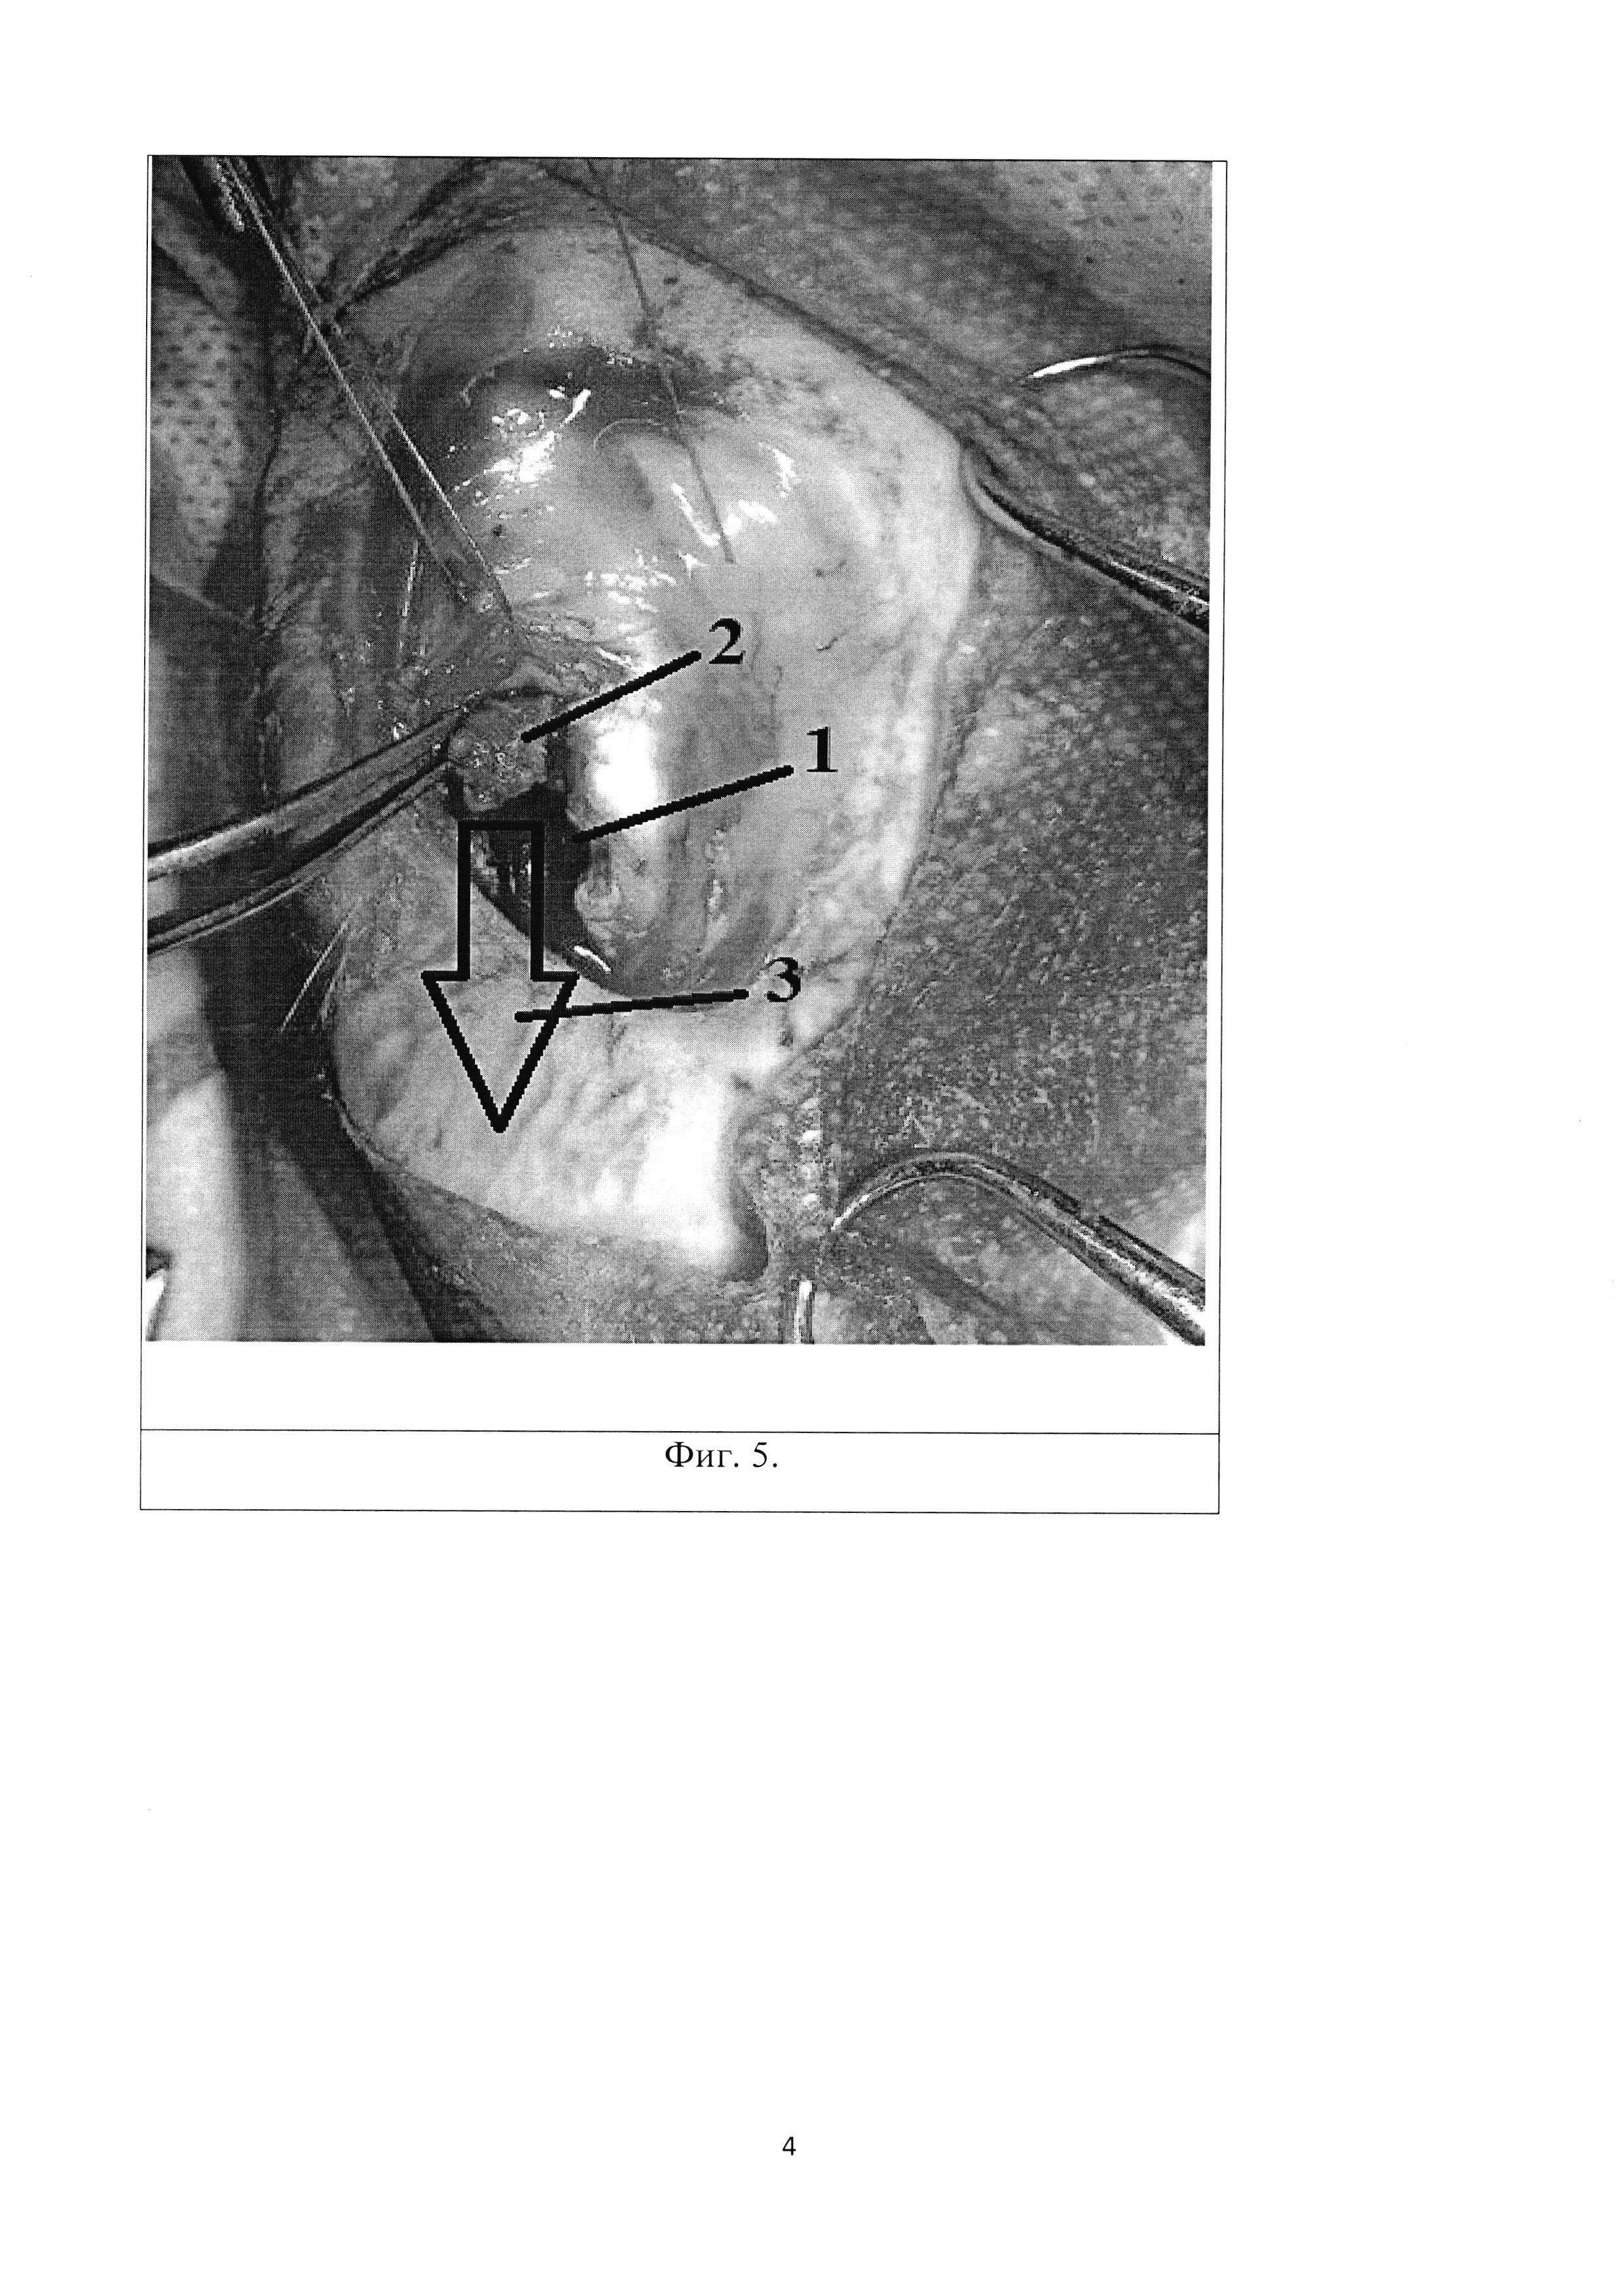

Изобретение относится к экспериментальной медицине, а именно к травматологии и ортопедии, и может быть применимо для изучения пато- и морфогенеза внутрисуставного импрессионного перелома и разработки способов хирургического лечения импресионного перелома эпифиза длинной трубчатой кости. По данным ряда авторов, внутрисуставные переломы в области коленного сустава составляют от 1,5 до 6,9% от всех переломов костей скелета и 10-12,2% от всех внутрисуставных переломов, а переломы мыщелков большеберцовой кости, относящиеся к тяжелым внутрисуставным повреждениям, составляют около 7% от всех переломов опорно- двигательного аппарата. Данный вид повреждений часто сопровождается импрессией костной ткани со стороны суставной поверхности и повреждением важных мягкотканых структур, что следует из особенностей строения сустава (отсутствие значительной мышечной массы, близкое расположение магистральных сосудов, нервов) и сложности его кинематики (Embden D., Stollenwerck G.A., Koster L.A., 2015). Актуальность разработки методов изучения внутрисуставных переломов определяется тем, что для переломов проксимального отдела болыпеберцовой кости характерна высокая частота неблагоприятных функциональных исходов: нередко в отдаленном периоде после травмы развивается деформирующий остеоартроз, контрактуры, нестабильность коленного сустава. Известен способ моделирования субкапитального перелома бедренной кости (Патент G09B 23/28, Способ моделирования субкапитального перелома бедренной кости. Патентообладатель Государственное бюджетное образовательное учреждение высшего профессионального образования Читинская государственная медицинская академия Министерства здравоохранения и социального развития Российской Федерации (RU). Заявка 2490721, Заявл. 2012-02-17, Опубл. 20.08.2013. - 6 с.), при котором обеспечивают равномерное сдавление шейки бедренной кости хирургическим зажимом типа «Москит» до создания субкапитального перелома. Однако данный способ не соответствует картине истинного, так как прикладываемая на кость энергия бранш рабочей поверхности зажима не может точно соответствовать таковой при истинном переломе, по той причине, что истинный перелом предполагает некую осевую перегрузку, возлагаемую на кость. Также данный метод является наиболее травматичным исходя из того, что двустороннее сдавление живой кости может привести к избыточному размозжению костной ткани, а рассечение капсулы тазобедренного сустава может обусловить развитие асептического некроза головки бедренной кости ввиду нарушения ее кровоснабжения. Также следует отметить, что пример субкапитального перелома бедренной кости не соответствует картине импрессионного перелома. Известен способ моделирования несрастающихся переломов длинных трубчатых костей, при котором производят поперечную остеотомию трубчатой кости в ее самом узком месте с помощью пилы Джигли (Патент 2323694, А61В 17/56, Способ моделирования несрастающихся переломов длинных трубчатых костей. Патентообладатель ФГОУ ВПО Белгородская государственная сельскохозяйственная академия. Заявка 2005135524, Заявл. 15.11.2005, Опубл. 10.05.2008. - 6 с.). Однако перелом не соответствует картине истинного ввиду создания его с помощью пилы. Кроме того, данный метод является наиболее травматичным исходя из того, что проволочное витое полотно пилы Джигли обладает слишком большой толщиной (0,5 мм), что может обусловить слишком грубый и избыточный распил кости. Тем самым не отражается этиопатогенез перелома кости. Также следует отметить, что пример субкапитального перелома бедренной кости не соответствует картине импрессионного перелома. Известен способ создания перелома кости в эксперименте, сущность которого состоит в том, что после обезболивания линейным разрезом обнажают поверхность кости на участке предполагаемого перелома (Патент SU 547211, 2 А61В 17/00, Способ создания перелома кости в эксперименте. Патентообладатель Московский городской ордена Трудового Красного Знамени институт скорой помощи им. И.В. Склифосовского. Заявка 1929378/13, Заявл. 28.05.73, Опубл. 25.02.77.). С помощью ножовочного полотна производят надпиливание кортикальной пластинки кости в поперечном направлении в области предполагаемой линии излома. Надпиливание кости производят на глубину кортикального слоя, создавая таким образом зону наименьшей сопротивляемости кости физическим нагрузкам. Захватывают сегмент конечности на протяжении резким ротирующим (при косом расположении линии надпила) или изгибающим (при поперечном надпиле) усилием, производят перелом кости. Однако при данном способе истинный перелом получают только на участке кости на стороне противоположной надпилу, что не соответствует патомеханике травматического перелома. Также данная методика является наиболее травматичной, так как излом кости производиться вручную и сила, прикладываемая к конечности, ничем не контролируема, что может привести к избыточному сгибанию конечности и травме мягких тканей. Нужно сказать, что данный способ моделирования перелома не соответствует картине импрессионного перелома кости. Прототипом данного изобретения стали истинные этиопатогенетические механизмы импрессионного перелома губчатых структур эпифиза любой длинной трубчатой кости. Кортикальная пластинка кости обладает большей, по сравнению с губчатым веществом, площадью цельной поверхности и, следовательно, большей упругостью. Когда на поверхность кортикальной пластинки воздействует определенная однонаправленная сила, запредельная по отношению к трабекулярному веществу, но недостаточная для разрушения компактного, трабекулы губчатого вещества начинают деформироваться и ломаться, а компактное вещество кости начинает заполнять этот объем дефекта, в результате чего образуется импрессионный дефект без четких границ. Технический результат: способ моделирования является высоковоспроизводимым и позволяет приблизить модель к реальному механизму развития патологического процесса. Для создания модели импрессионного внутрисуставного перелома проксимального отдела большеберцовой кости наиболее приближенной к истинной, производится четырехсторонний распил кости (8×7 мм) 1 в области медиального мыщелка большеберцовой кости (Фиг. 1, Фиг. 4) алмазным металлическим отрезным диском (d=10 мм, толщиной = 1,5 мм), отступя 3-5 мм от суставной поверхности дистально. Образовавшийся прямоугольный участок кости извлекается при помощи зажима по типу «москит». Далее производится надлом и смещение части мыщелка 2 (Фиг. 2, Фиг. 5) в дистальном направлении 3 (Фиг. 2, Фиг. 5) в область костного дефекта 1 (Фиг. 2, Фиг. 5), в результате чего образуется импрессионный внутрисуставной перелом медиального мыщелка проксимального отдела большеберцовой кости 4 (Фиг. 3, Фиг. 6, Фиг. 7). Изобретение поясняется иллюстрациями, на которых представлена поэтапная схема проведения внутрисуставного импрессионного перелома. На Фиг. 1. изображен выпиленный прямоугольный участок кости 1 (8×7 мм), который на дальнейших этапах операции будет извлекаться, освобождая под собой вход в костномозговой канал. На Фиг. 2. обозначено направление смещения эпиметафизарного участка с образованием истинного импрессионного дефекта суставной поверхности медиального мыщелка большеберцовой кости, где: 1 - выпиленный прямоугольный участок кости, 2 - часть мыщелка, 3 - направление смещения. На Фиг. 3. изображена готовая модель истинного внутрисуставного импрессионного перелома 4. Фиг. 4. На фотографии виден прямоугольный участок выпиленной кости 1 (8×7 мм), который извлекался, освобождая вход в костномозговой канал. Фиг.5. На фотографии виден смещенный проксимальнее участок медиального мыщелка большеберцовой кости, где: 1 - выпиленный прямоугольный участок кости, 2 - часть мыщелка, 3 - направление смещения. Фиг. 6. На фотографии виден результат операции по моделированию внутрисуставного импрессионного перелома 4, которая окончилась смещением медиального мыщелка большеберцовой кости дистальнее суставной поверхности. Фиг. 7. На фронтальном и сагиттальном КТ-срезе коленного сустава кролика виден результат операции по моделированию внутрисуставного импрессионного перелома 4 медиального мыщелка проксимального отдела большеберцовой кости, имеется область импрессии и дисконгруэнтности суставной поверхности. Способ осуществляют следующим образом. Животное погружают в наркоз и обрабатывают область оперативного вмешательства, выполняют доступ к медиальному мыщелку большеберцовой кости путем острой диссекции мягких тканей с внутренней стороны голени. Мягкие ткани разводятся, в результате чего обеспечивается доступ к участку кости с надкостницей; костным распатором Фарабефа надкостница сдвигается в дистальном направлении. Анатомическим ориентиром для дальнейших действий является общее сухожильное крепление мышц внутренней поверхности бедра - «поверхностная гусиная лапка». Алмазным металлическим отрезным диском (d=10 мм, толщиной = 1,5 мм) производится четырехсторонний распил кости (7×8 мм) 1 в области медиального мыщелка большеберцовой кости (Фиг. 1, Фиг. 4) перед вышеуказанным анатомическим образованием, на глубину кортикальной пластинки кости, без проникновения в полость коленного сустава. Извлекается прямоугольный участок кости. Производится смещение мыщелка 2 (Фиг. 2, Фиг. 5) в дистальном направлении 3 (Фиг. 2, Фиг. 5) в область образовавшегося костного дефекта (Фиг. 2, Фиг. 5) для обеспечения дисконгруэнтности суставной поверхности (Фиг. 3). Рана послойно ушивается. Способ моделирования внутрисуставного импрессионного перелома большеберцовой кости иллюстрируется следующим примером. Пример Для выполнения модели был взят кролик породы «Шиншилла» массой 2600 грамм. При работе с животным соблюдались «Международные рекомендации (этический кодекс) по проведению медико-биологических исследований с использованием животных» (1985). После погружения животного в парентеральный наркоз и традиционной обработки операционного поля был выполнен разрез кожных покровов, тупым и острым способом был осуществлен доступ к медиальному мыщелку большеберцовой кости. После разведения мягких тканей, костным распатором Фарабефа надкостница сдвигалась дистально. Далее алмазным металлическим отрезным диском производился четырехсторонний распил кости перед сухожильным расширением «Гусиная лапка». Участок выпиленной кости извлекался и производилось смещение мыщелка в дистальном направлении в область образовавшегося костного дефекта для обеспечения дисконгруэнтности суставной поверхности. Рана послойно ушивалась. Таким образом, предлагаемый способ моделирования является высоко воспроизводимым и позволяет приблизить модель к реальному механизму развития патологического процесса. В ходе эксперимента была сделана серия снимков на КТ аппарате Toshiba Aquilion 64, пример данного снимка представлен на Фиг. 7.